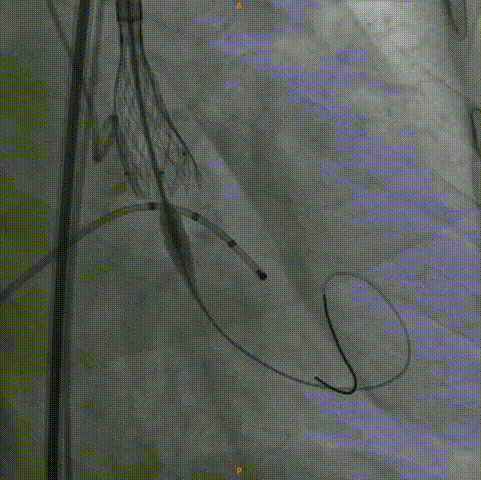

主动脉根部造影:左右冠灌注情况良好,瓣叶活动度一般,无明显反流。

20mm球囊预扩:冠脉灌注情况良好,瓣上结构改变,微量反流。

Venus26号瓣膜定位:结合瓣上结构考虑,采用0位释放。

Venus26号瓣膜释放:前三分之一慢放精准定位,中三分之一快放使瓣膜快速进入工作状态。

Venus26号瓣膜释放:位置良好,轻度反流,遂完全释放后采取后扩。

后扩后瓣膜最终形态。